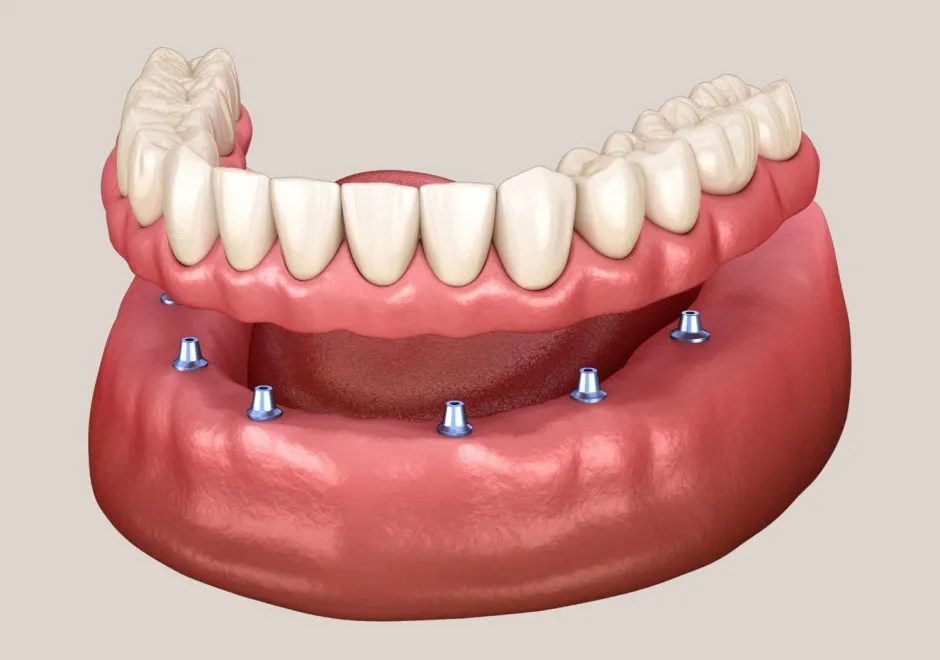

Der Vorteil des ALL-ON-4® Verfahrens liegt darin, dass mit nur 4 miteinander verbundenen Implantaten pro Kiefer eine festsitzende Brücke direkt nach dem Entfernen der nicht mehr erhaltungswürdigen Zähne eingesetzt werden kann. In der Regel kann auf eine provisorische Versorgung verzichtet werden, was dem Patienten erhebliche Kosten für den provisorischen Zahnersatz (ca. 1500 CHF pro Kiefer) spart.

Dank einer speziellen Einsetz-Technik der Implantate und einer 3-dimensionalen computergestützten Planung ist dies auch bei Patienten mit stärkerem Knochenabbau (z.B. durch jahrelanges Tragen einer Totalprothese oder nach einem Unfall) möglich, die sonst aufwendige Knochenaufbauten benötigen würden.